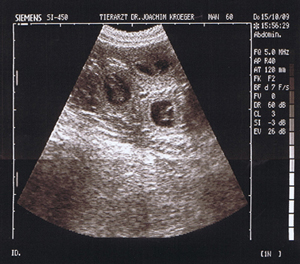

15.10.2009 heute war die Ultraschalluntersuchung:

wir waren sehr glücklich, dass sich unsere Vermutungen bestätigt

haben - Milly ist trächtig!

6 kleine "Blubberblasen" haben wir schon

gesehen, aber es sind sicher noch mehr :-)